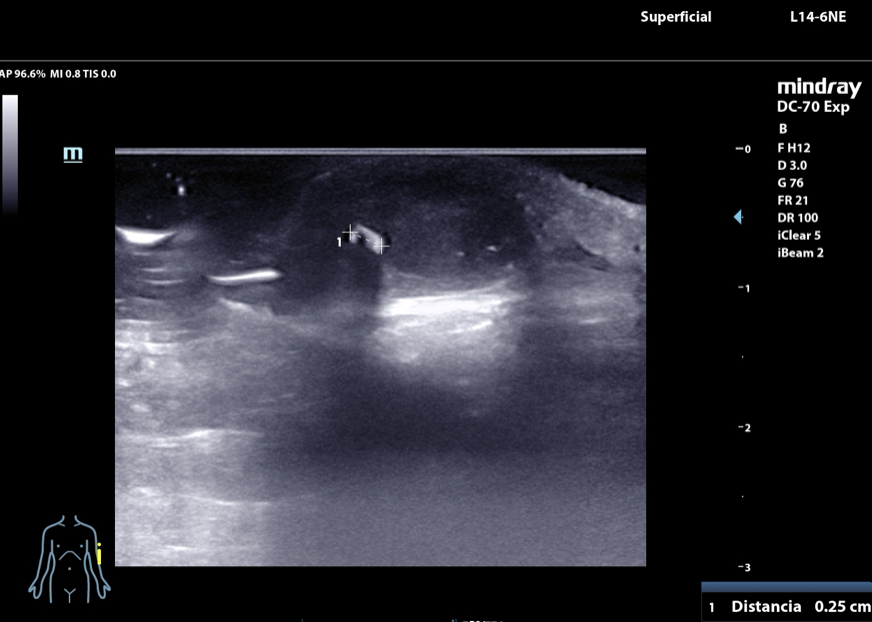

Hombre de 17 años que acude a consulta en agosto de 2024 por dolor y tumefacción a nivel de epicóndilo de codo izquierdo. En abril sufrió una caída contra una palmera y desde ese momento ha consultado hasta en tres ocasiones en Urgencias por dolor. En el informe de urgencias se diagnostica un absceso cutáneo de 1 cm de diámetro y se solicita una radiografía de codo (sin alteraciones). Se alta con antibioterapia. En consulta persiste la sintomatología. Se revisa la radiografía y se repite la exploracion física: tumefacción de 1,5 cm de diámetro en epicóndilo izquierdo. Se decide realizar una ecografía músculoesquelética con identificación de un cuerpo extraño tras lo que se procede a su extracción que resulta ser una púa de 2,6 cm.

Descripción de los hallazgos ecográficos y las imágenes más relevantes para la resolución del caso

Al inicio se sospechaba una reacción cutánea a cuerpo extraño no evidenciado en radiografía que se confirmó mediante ecografía.

Diagnóstico final: reacción cutánea a cuerpo extraño (púa de palmera).

Tras la ecografía se procede a la extracción de dicho cuerpo extraño que resulta ser una púa de palmera de 2,6 cm de longitud.

La ecografía es una prueba complementaria accesible desde Atención Primaria, inocua y rápida que permite la identificación de estructuras que, como la descrita en el caso clínico, resultan invisibles a la radiografía convencional, lo cual favorece el logro de diagnósticos más certeros que evitan medidas terapéuticas futiles y la cronificación del dolor musculoesquelético.